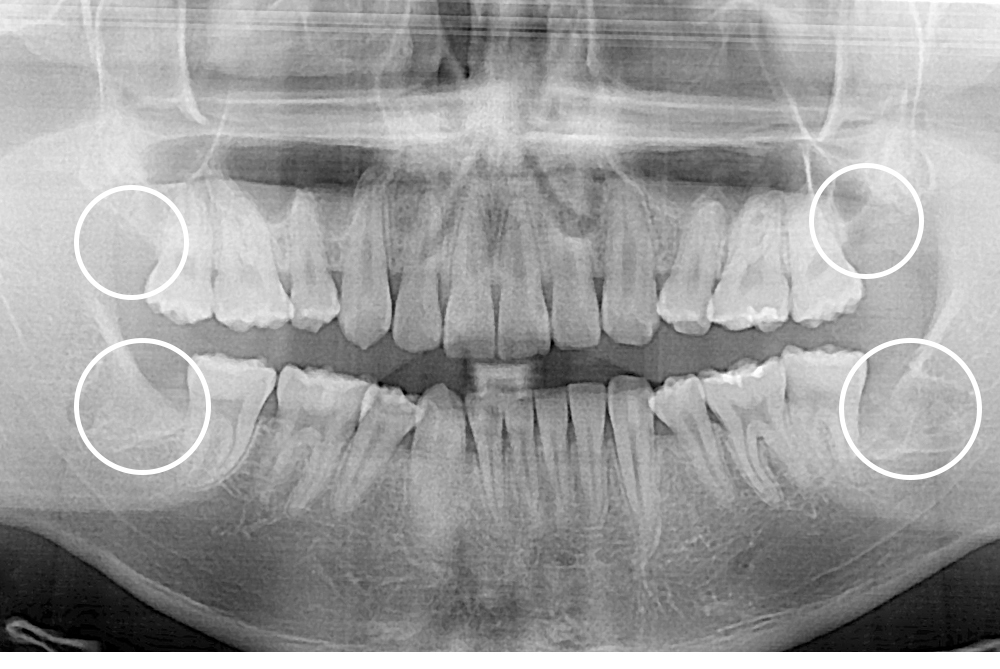

[사랑니] 매복 사랑니 발치

치료후 : 2020-11-17

세종치과는 구강악안면외과학 박사이신 원장님이 발치하는 치과입니다.